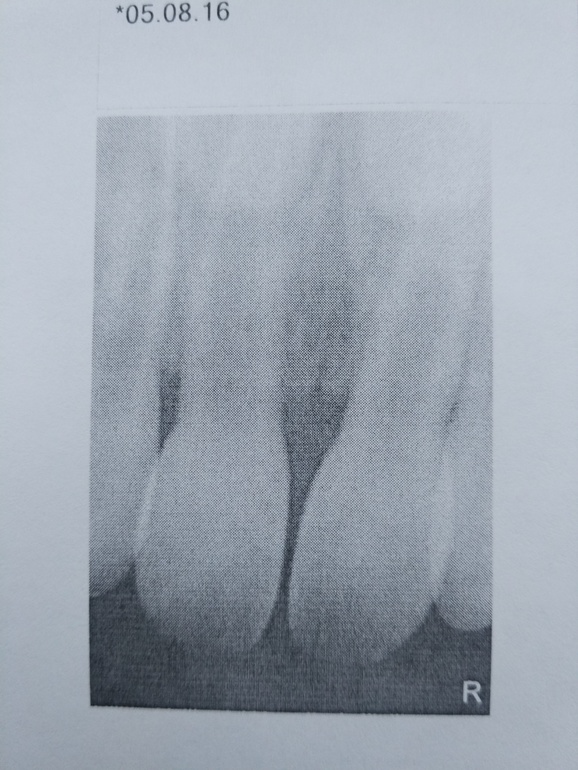

ЗубкиUPD. Сходили сегодня с сыном к стоматологу. У него действительно покривился зуб после падения. Сделали рентген. На снимке видно, что справа зуб смещён и изогнут, раньше такого не было. Ещё хорошо, что нет переломов и корни, нервы целы, иначе бы вырывали зуб! А так врач рекомендовала на 2-3 недели отказаться от твёрдой пищи, неделю обрабатывать раны ромашкой, Мирамистином и гелем Холисал. Наблюдать, не будет ли изменений в зубе.